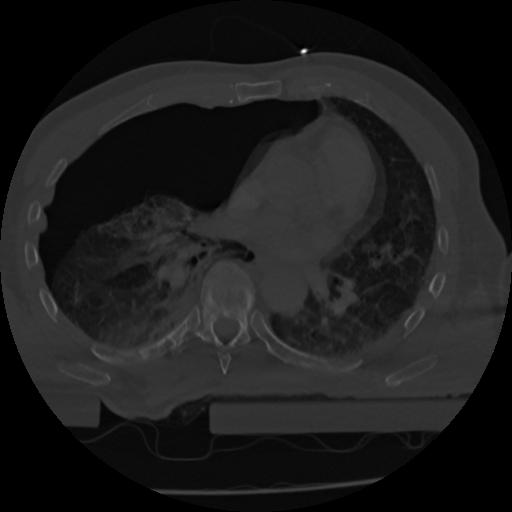

22 ANGIO,CE,Vol,0.5,ANGIO,,